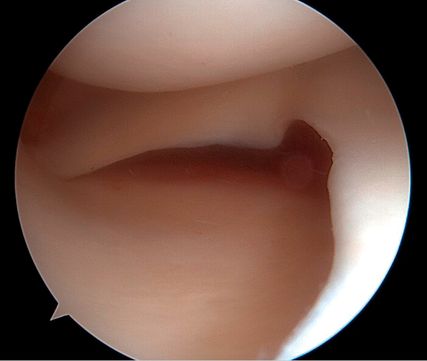

Kombinierte Verletzungen des medialen Kollateral- (MCL) und des vorderen Kreuzbandes (VKB) zählen zu den häufigsten multiligamentären Knieverletzungen. Bei vermeintlich isolierten VKB-Rupturen werden MCL-Verletzungen häufig unterschätzt bzw. nicht diagnostiziert. Dadurch kommt es nach VKB-Rekonstruktion und medialer Instabilität zu vermehrten VKB-Rerupturen. Eine optimale Therapie der anteromedialen Rotationsinstabilität (AMRI) erfordert daher eine detaillierte Diagnostik.

Isolierte oder kombinierte Verletzungen des medialen Kollateralbandes sind häufig. Zunehmende Evidenz zeigt, dass eine residuelle MCL-Laxität zu nachfolgenden Meniskus- und Knorpelschäden sowie zu einer erhöhten Belastung des VKB bzw. der VKB-Plastik führen kann, was wiederum das Risiko für eine VKB-Reruptur erhöht. Die aktuellen Therapiestrategien der AMRI variieren und umfassen sowohl operative als auch konservative Behandlungsansätze. Ein Konsens hinsichtlich Diagnostik, Klassifikation und Therapie der AMRI fehlt bislang aufgrund der begrenzten klinischen Studienlage.